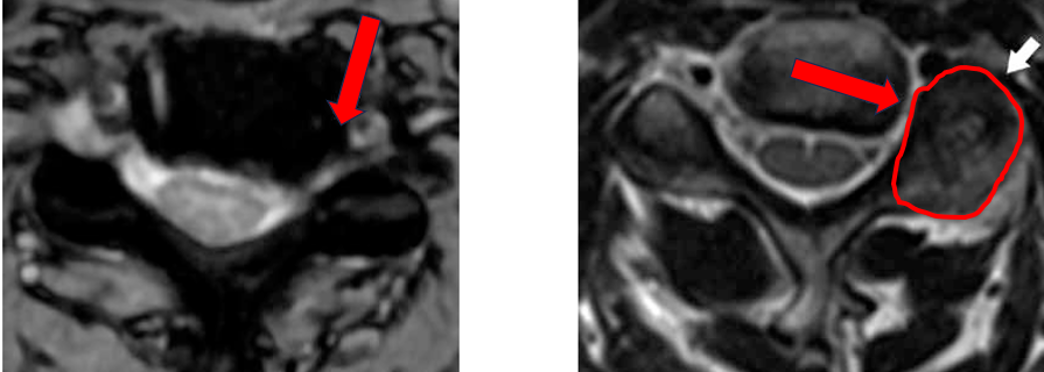

Surgery on the neck part of the spine to relieve pressure on the spinal cord or nerves.

Who Needs This Surgery?

- Patients with severe neck pain

- Pain spreading to arms

- Tingling or weakness in hands

- Walking imbalance due to spinal cord pressure